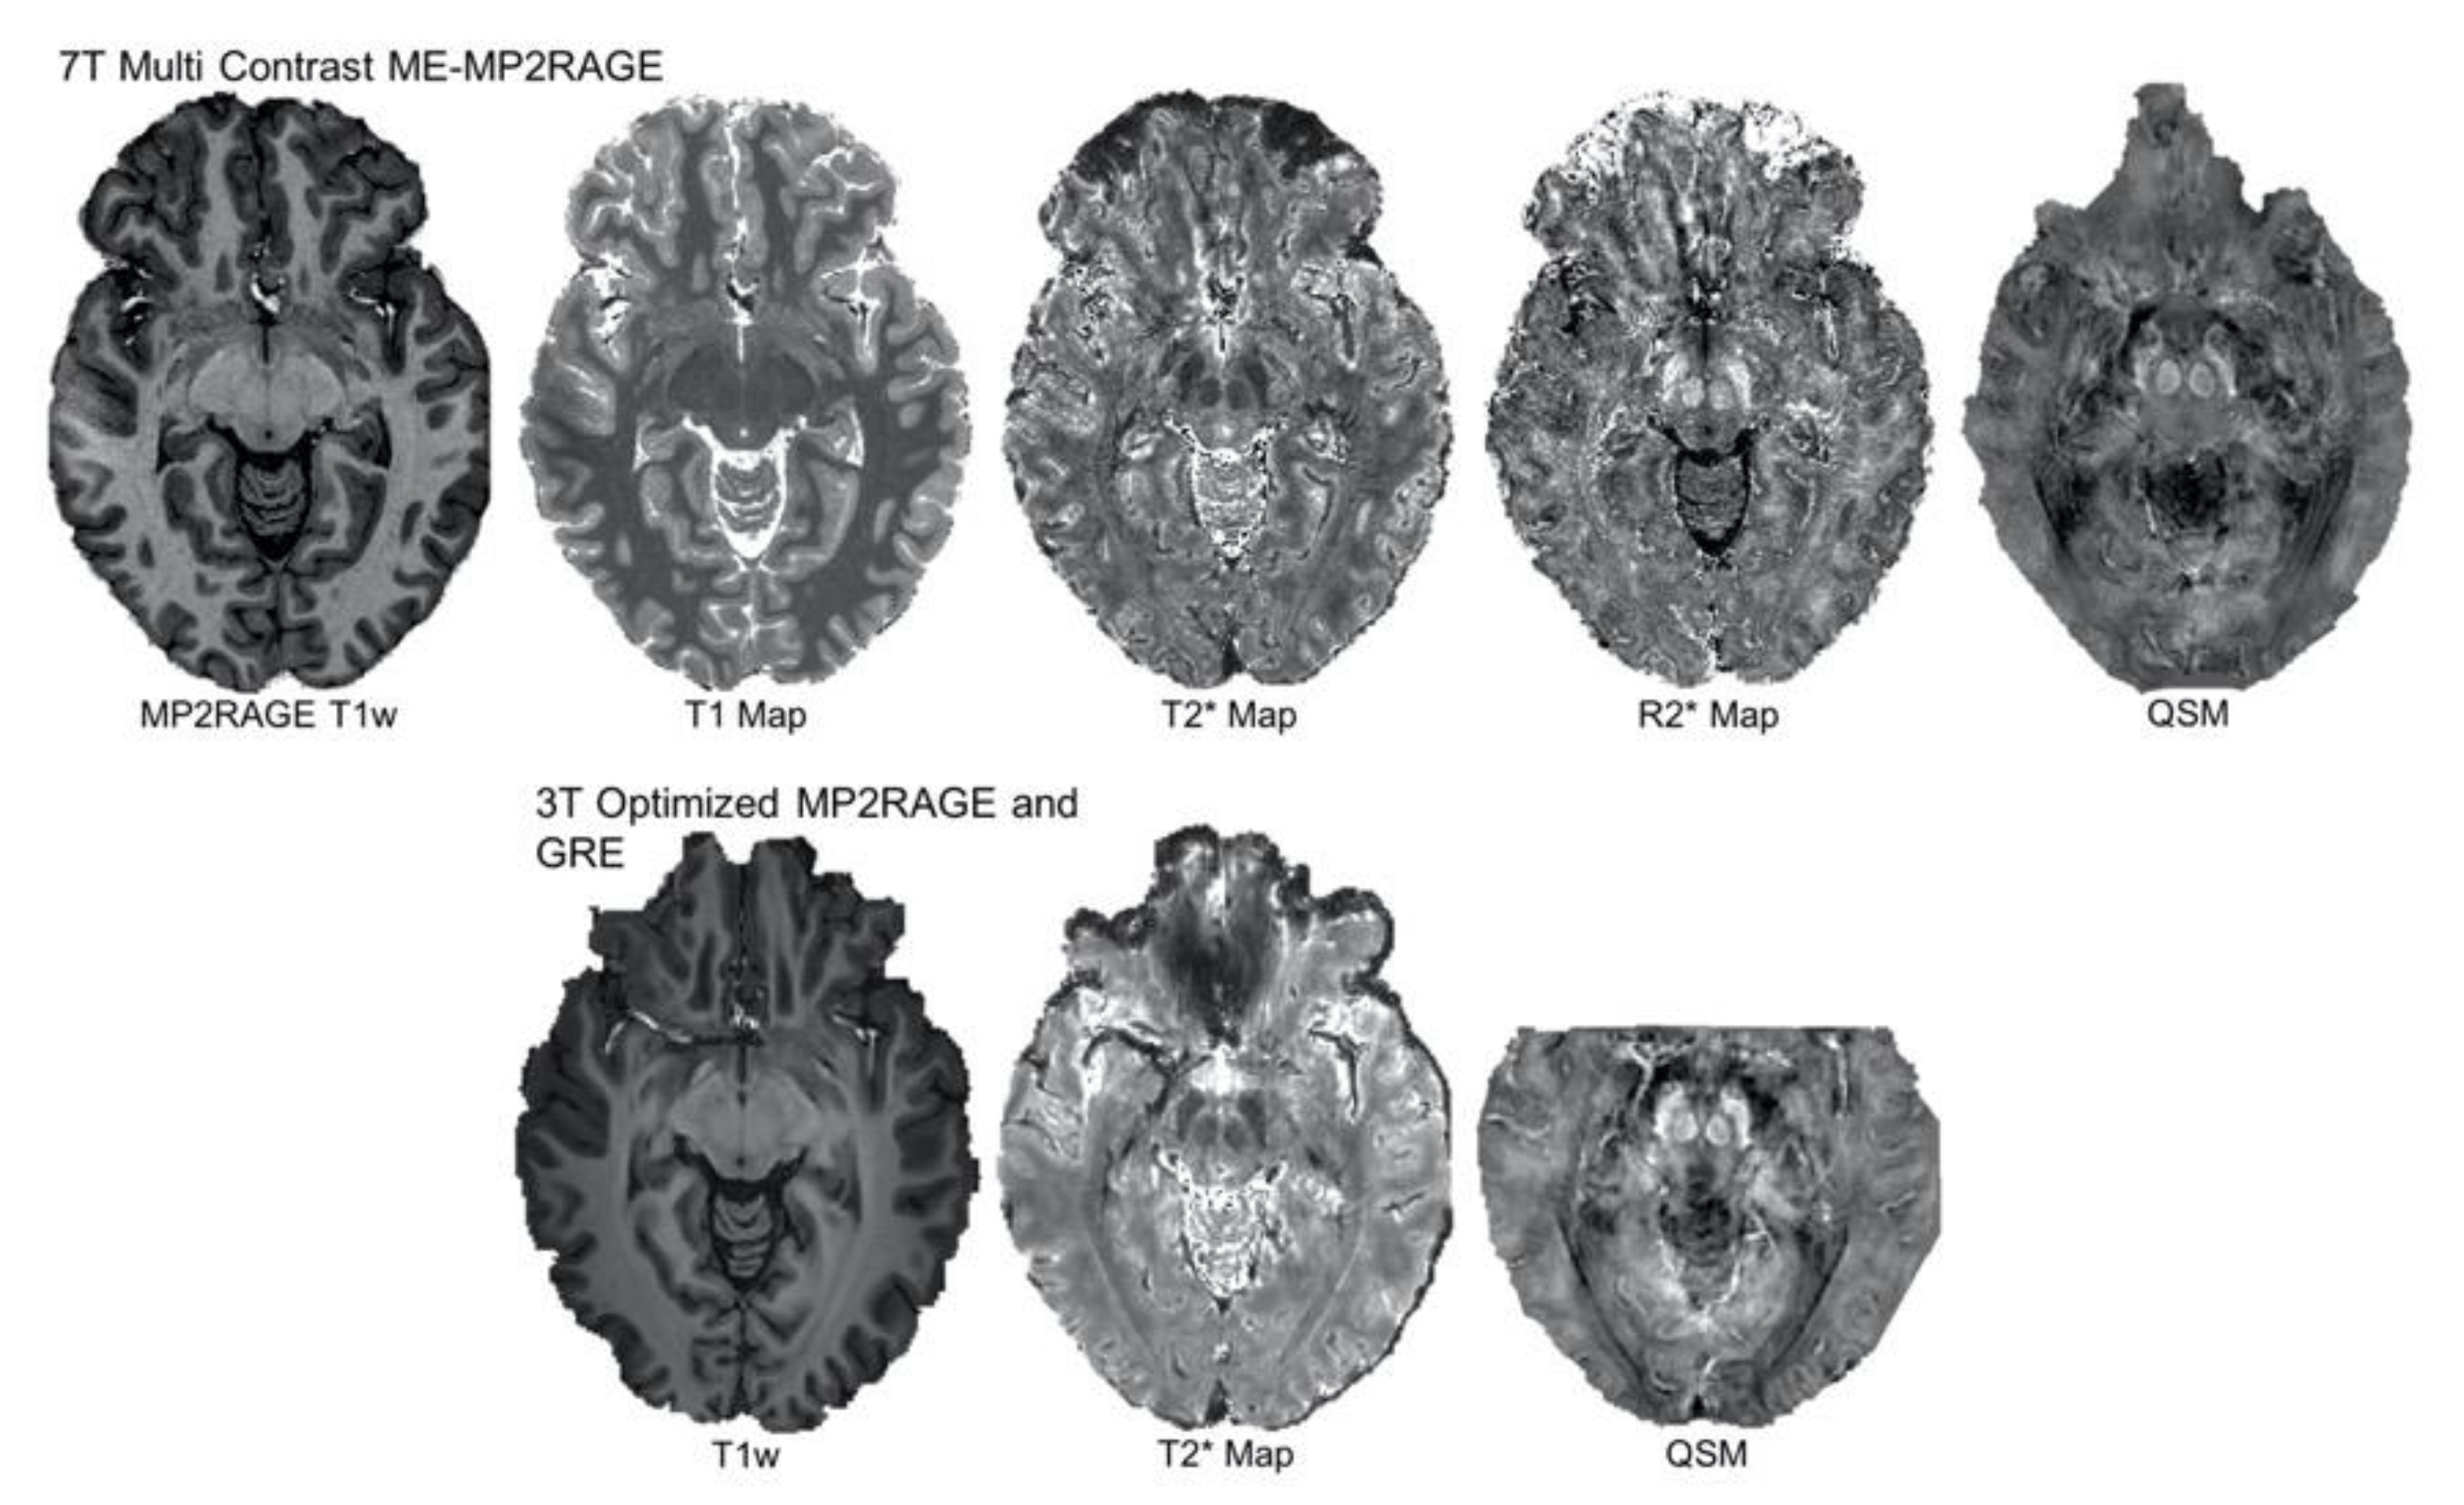

- Sun, H.; Cleary, J.O.; Glarin, R.; Kolbe, S.C.; Ordidge, R.J.; Moffat, B.A.; Pike, G.B. Extracting more for less: Multi-echo MP2RAGE for simultaneous T1-weighted imaging, T1 mapping, R2∗ mapping, SWI, and QSM from a single acquisition. Magn. Reson. Med. 2020, 83, 1178–1191. [Google Scholar] [CrossRef] [PubMed]

- Metere, R.; Kober, T.; Möller, H.E.; Schäfer, A. Simultaneous quantitative MRI mapping of T1, T2* and magnetic susceptibility with multi-echo MP2RAGE. PLoS ONE 2017, 12, e0169265. [Google Scholar] [CrossRef]

- Bazin, P.L.; Alkemade, A.; Van Der Zwaag, W.; Caan, M.; Mulder, M.; Forstmann, B.U. Denoising high-field multi-dimensional MRI with local complex PCA. Front. Neurosci. 2019, 13, 1066. [Google Scholar] [CrossRef]

- Isaacs, B.R.; Mulder, M.J.; Groot, J.; Van Berendonk, N.; Lute, N.; Bazin, P.L.; Forstmann, B. 3 versus 7 Tesla MRI for parcellations of subcortical brain structures. bioRxiv 2020. under review. [Google Scholar]